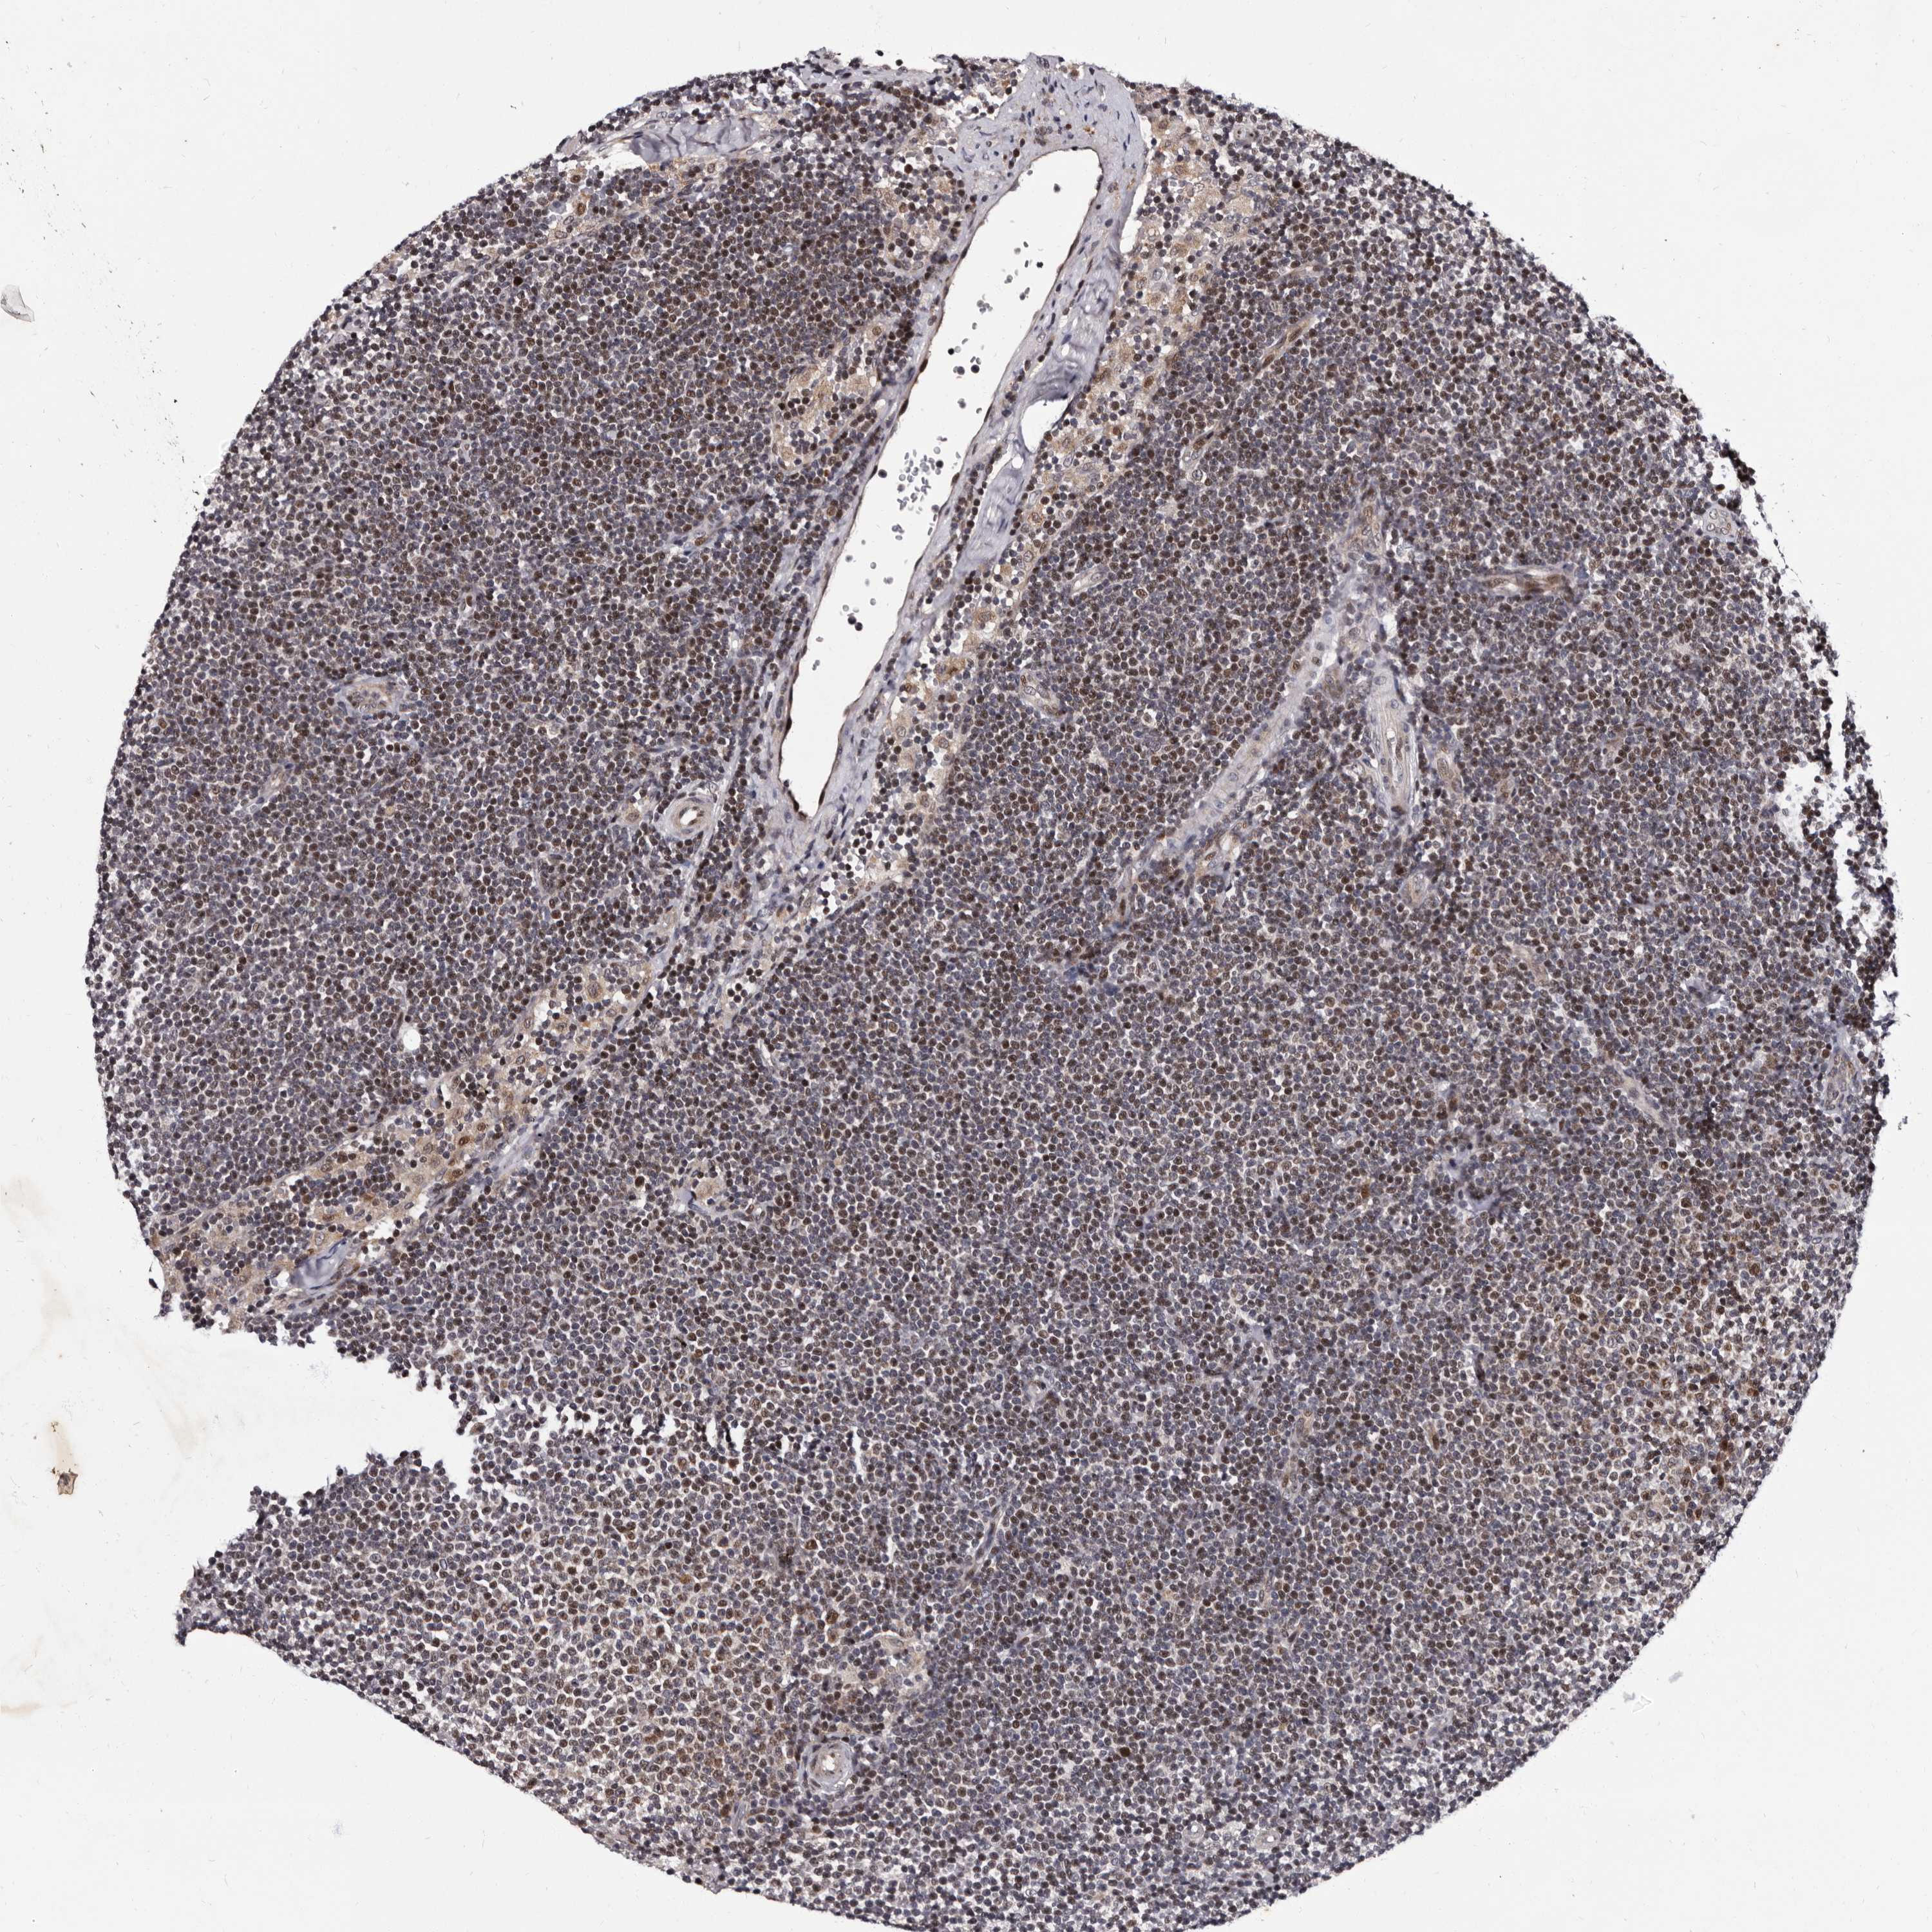

CANCER LYMPHOMA Show tissue menu

LYMPHOMA - Protein expressioni

A mouse-over function shows sample information and annotation data. Click on an image to view it in a full screen mode. Samples can be filtered based on level of antibody staining by selecting one or several of the following categories: high, medium, low and not detected. The assay and annotation is described here.

Antibody stainingi

Antibody staining in the annotated cell types in the current human tissue is reported as not detected, low, medium, or high, based on conventional immunohistochemistry profiling in selected tissues. This score is based on the combination of the staining intensity and fraction of stained cells.

Each image is clickable and will lead to virtual microscopy that enables deeper exploration of all samples and also displays staining intensity scores, fraction scores and subcellular localization as well as patient and tissue information for each sample.

Antibody HPA025690

Staining

High

Medium

Low

Not detected

Intensity

Strong

Moderate

Weak

Negative

Quantity

>75%

75%-25%

<25%

None

Location

Nuclear

Cytoplasmic/membranous

Cytoplasmic/membranous,nuclear

Hodgkin's disease, NOS

Malignant lymphoma, non-Hodgkin's type, High grade

Malignant lymphoma, non-Hodgkin's type, Low grade